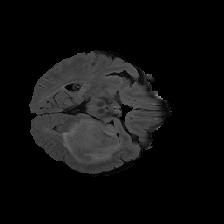

Brain tumor segmentation. Segmenting tumors in brain is challenging due to the high variance in appearance and shape of the tumors [28]. We use a subset of the 2017 Brain Tumour Image Segmentation (BraTS) dataset [29, 26]. It contains multi-parametric 3D MRI scans. The segmentation masks include (possibly overlapping) three classes of tumor. The 3D scans are split into 2D image slices, and only images that contain at least one tumor class are retained. Figure 7 shows three MSGNet generated samples as well as the corresponding masks. Since MSGNet adheres to the underlying relationships between various classes, we see that the generated images and the masks for different tumor classes are in line with the images and masks from the training set. In general, MSGNet rarely generated erroneous samples; we found roughly one sample per 3000 generations that could be rejected. Similar to the malaria experiment, we observed an improvement of 3.1% () in -score on the validation set.

A subset of the BrATS dataset was used. We used the images accompanied by segmentation layouts from the FLAIR and T1Gd modes. The segmentation layouts showed the sub-regions for three different classes: GD-enhancing tumor, the peritumoral edema, and the necrotic and non-enhancing tumor core. The brain and the background were treated as an additional class. We refer to [32] for further details. For the two modes, the background has been modelled using two different classes. We only considered half of the 155 slices, i.e., we took only the even-numbered slices and out of those we discarded the slices that did not include one of the previously mentioned tumor-classes in order to create a more balanced dataset. This resulted in 20,000 images that were further augmented with 6,000 MSGNet generated images. Example generations of the masks as well as the images are shown in Figure 12.